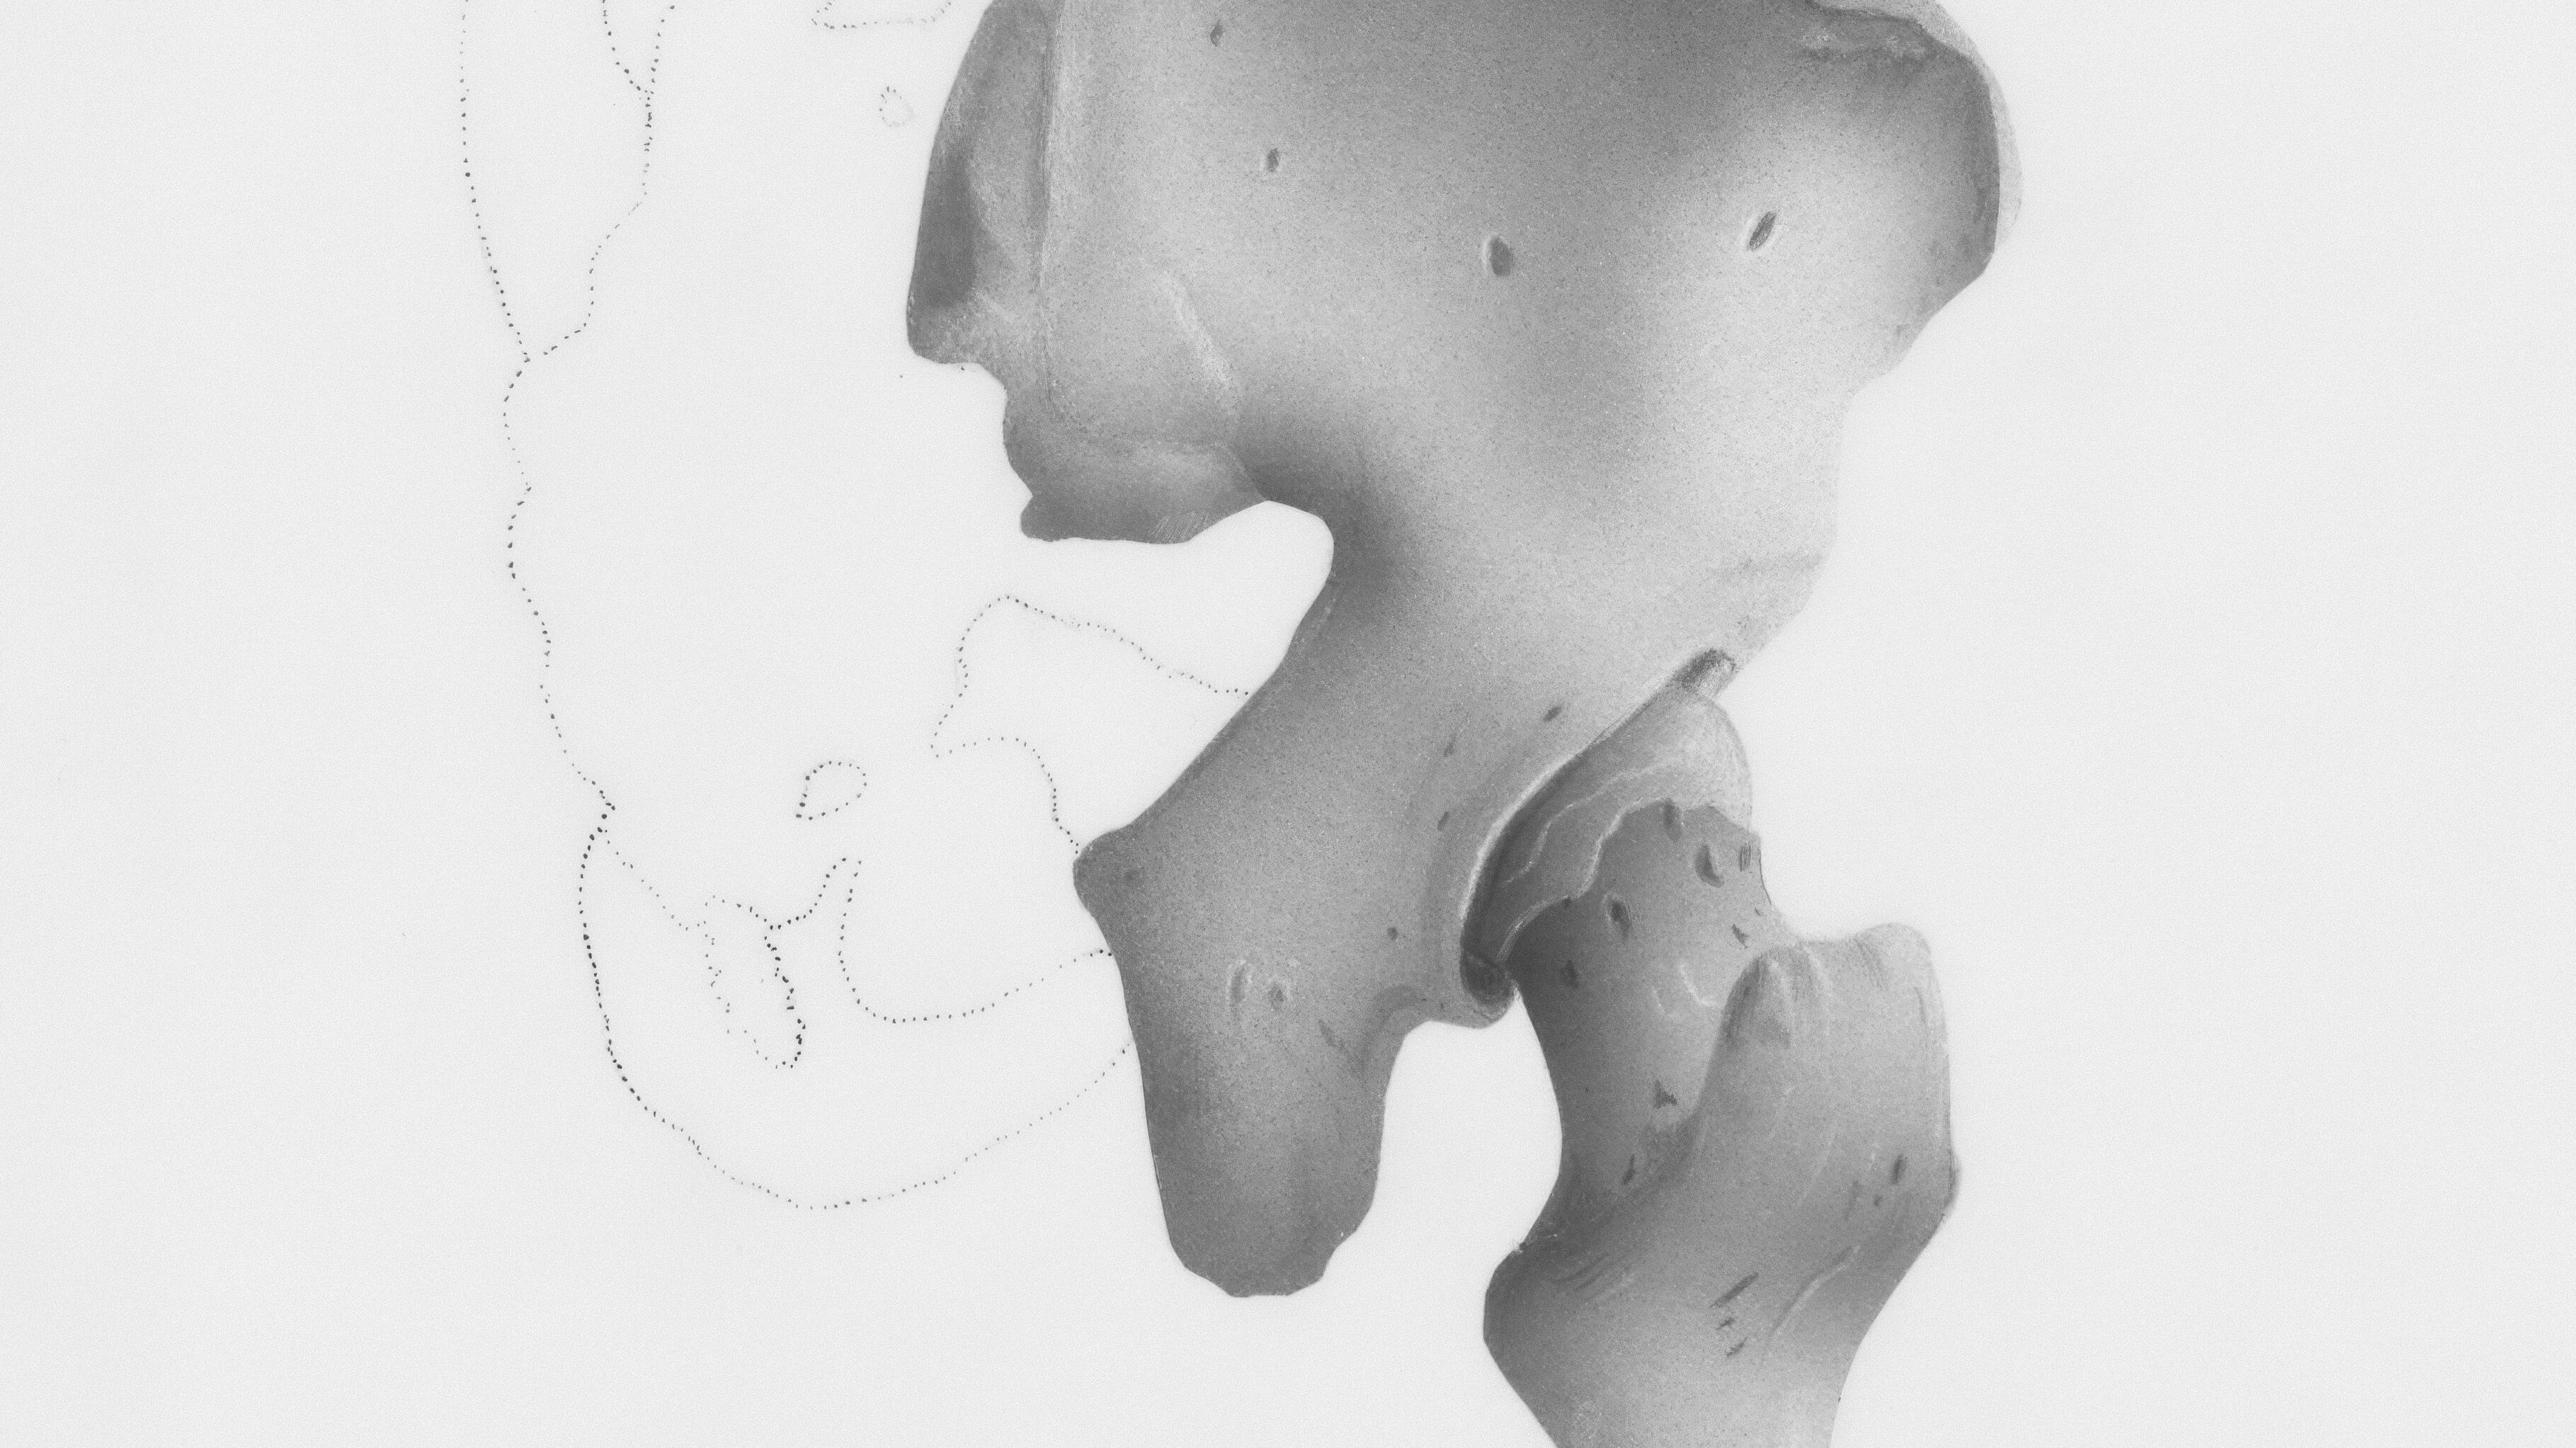

2. 真犯人①:ガチガチの股関節が腰を引っ張る

腰痛持ちの人の100%と言っても過言ではない共通点が、股関節の硬さです。

2-1. 反り腰を生む「腸腰筋」の短縮

太ももの付け根にある腸腰筋が固まると、骨盤を前へギュッと引っ張ります。すると、腰の骨は無理やり反らされる形になり、常に「反り腰」状態に。これが、立っているだけで腰が痛くなる大きな原因です。